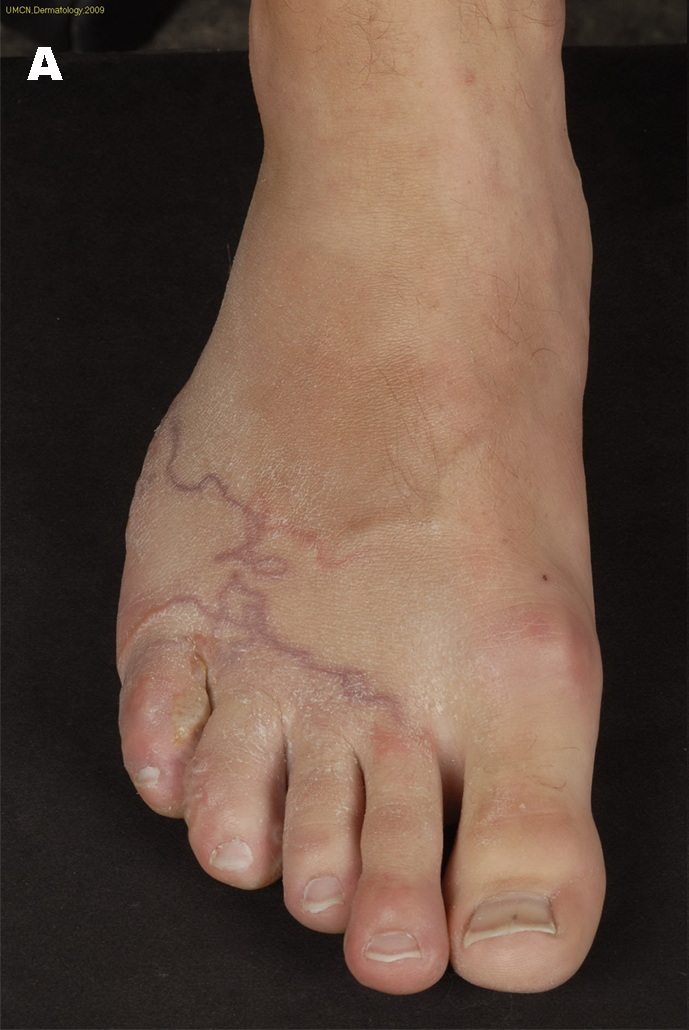

Nenhum dos dois médicos que eles foram identificaram o problema com os pés. Finalmente, o terceiro médico que visitaram conseguiu descobrir o problema. Ambos tinham parasitas chamados de larva migrans cutânea.

Para quem viaja em algum lugar tropical, tenha cuidado quando estiver na areia e use sapatos! Meu namorado e eu recentemente voltamos de Punta Cana para descobrir que ambos temos larva migrans, em outros termos, vermes em nossos pés.

Se seus pés se tornam incrivelmente pruridos, faça o check-up imediatamente, já que simplesmente pensamos que era apenas picadas de insetos e ficou pior à medida que os dias passavam.

De acordo com o American Osteopathic College of Dermatology, “Larva migrans cutânea, também conhecida como erupção rastejante ou larva migrânea, é um termo usado para descrever lesões de pele lineares tortuosas causadas por larvas. Pessoas que estão expostas ao solo e à areia são os mais infectados. Os pés, as mãos, as nádegas e os órgãos genitais são mais comumente afetados. Essas lesões podem coçar, pinicar e eventualmente causar dor “.

E se seus pés começam a ter uma coceira, ondulação ou bolha ou parecido com os meus, cheque imediatamente! Pode não ser o que o seu médico pensa.

Tudo isso apenas de andar com os pés descalços na praia. Então, qualquer pessoa que viaje .. verifique com seu resort e veja se as praias ao seu redor são limpas regularmente. E é melhor usar sapatos na praia o máximo possível!